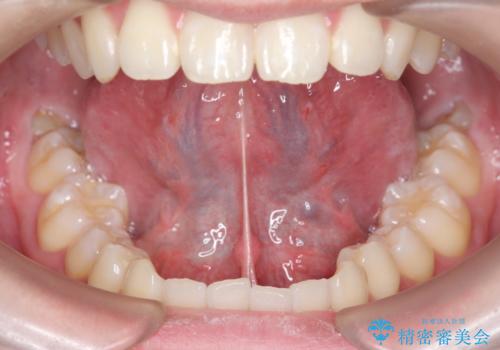

- 舌が動かしにくく、発音に支障があるため、舌小帯切除術を希望された方の症例です。

舌小帯は舌の下にある線維性のスジです。これが短かったり、強直していると、舌運動を上手く行えず、発音や咀嚼・嚥下等に弊害をきたす場合があります。

舌小帯を切除することで舌の可動域が広がり、上記の弊害を改善することが可能です。